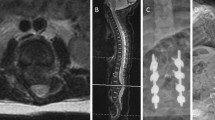

Magnetic resonance imaging (MRI) of the spine with and without contrast revealed a syrinx of the conus medullaris without other abnormalities (Fig. 1a). This was managed expectantly with repeat MRI at 12 months of age, which showed expansion of the syrinx and fatty infiltration of the filum terminale consistent with tethered spinal cord (Fig. 1b). Surgical release of the tethered cord was thus undertaken. The procedure was uneventful and the patient recovered well postoperatively. Follow-up MRI 8 months postoperatively showed slight decrease in the size of the syrinx (Fig. 1c). One year postoperatively, neurological examination remained nonfocal without any deficits referable to the tethered cord or surgical procedure. Motor and cognitive function were improved compared to initial presentation but with ongoing delay in meeting respective milestones.

Magnetic resonance imaging of the lumbosacral region. a Sagittal and axial T2-weighted scans at 6 months of age showing a syrinx of the conus medullaris. b Sagittal T2-weighted and axial T1-weighted scans at 12 months of age showing enlargement of the syrinx, borderline low-lying conus medullaris, and fatty infiltration of the filum terminale (arrowhead) consistent with tethered cord. c Sagittal T2-weighted scan 8 months after release of tethered cord showing decreased syrinx size